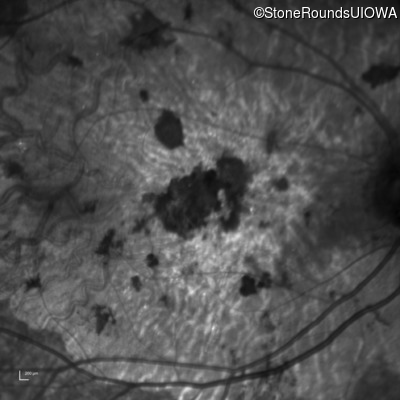

Infrared Fundus Photograph - Right - 20/250 sc

Exemplar